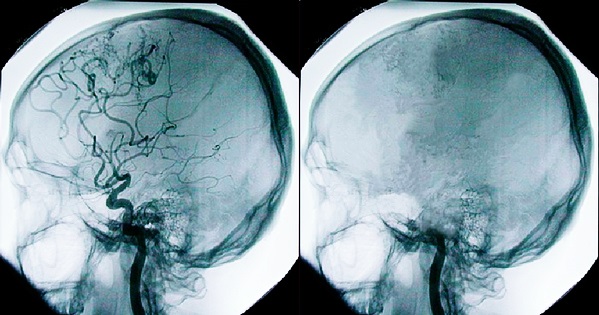

Инсульт – смертельно опасное заболевание, сопровождающееся нарушением кровоснабжения определенных участков головного мозга. В результате мозговые ткани не дополучают необходимое питание и кислородоснабжение, поэтому они начинают отмирать. Если инсульт обширный, то есть повреждена большая площадь головного мозга, страдают жизненно важные функции организма, за которые отвечают пораженные участки мозга. В тяжелых случаях наступает смерть после инсульта – самое опасное осложнение.

- Ишемический. Считается самым распространенным видом патологии. Развивается вследствие закупорки сосудов, по которым происходит кровоснабжение мозговых тканей, тромбом. В результате нарушается нормальное кровоснабжение клеток. Если первая помощь пострадавшему оказана несвоевременно, клетки полностью отмирают и больше не восстанавливаются.

- Геморрагический. При таком виде инсульта происходит повреждение сосуда, располагающегося в головном мозге. В результате кровь скапливается в мозговых тканях, сдавливая нервные волокна и нарушая нормальное кровоснабжение пораженных структур.

- Нетравматическое субарханоидальное кровоизлияние. Диагностируется редко, но такая патология считается смертельно опасной. При субарханоидальном кровоизлиянии кровь проникает в полость между паутинной и мягкой мозговой оболочкой. Даже если диагностика и лечение патологии проводятся своевременно, человек с большей долей вероятности остается на всю оставшуюся жизнь глубоким инвалидом.

- Аневризма сосудов головного мозга. Специфическое образование, которое имеет тонкую стенку. При стечении неблагоприятных факторов аневризма может в любой момент разорваться, что повлечет за собой геморрагический инсульт и тяжелые осложнения.